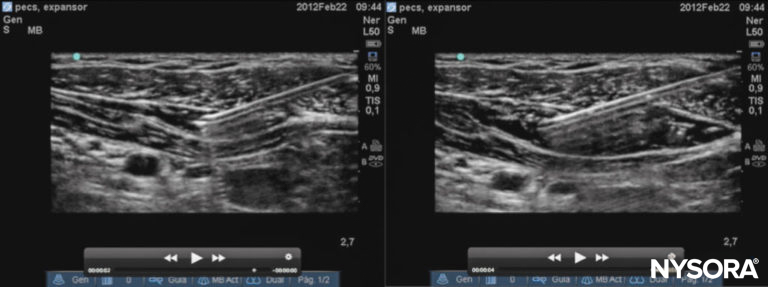

Figure 8. Sonogram of the Pecs I injection. Left: needle placement; right: desired spread of local anesthetic.

The transducer is then moved laterally until the pectoralis minor and serratus anterior are identified. With further lateral transducer movement, the third and fourth rib can then be identified. The local anesthetic is injected at two points: The first injection of approximately 0.2 mL/kg long-acting local anesthetic is made between the pectoral major and minor muscles, and the second injection of 0.2 mL/kg is made between the pectoralis minor and serratus anterior muscles. Figure 10 illustrates the sonographic anatomy, needle trajectory, and the desired spread of injectate.